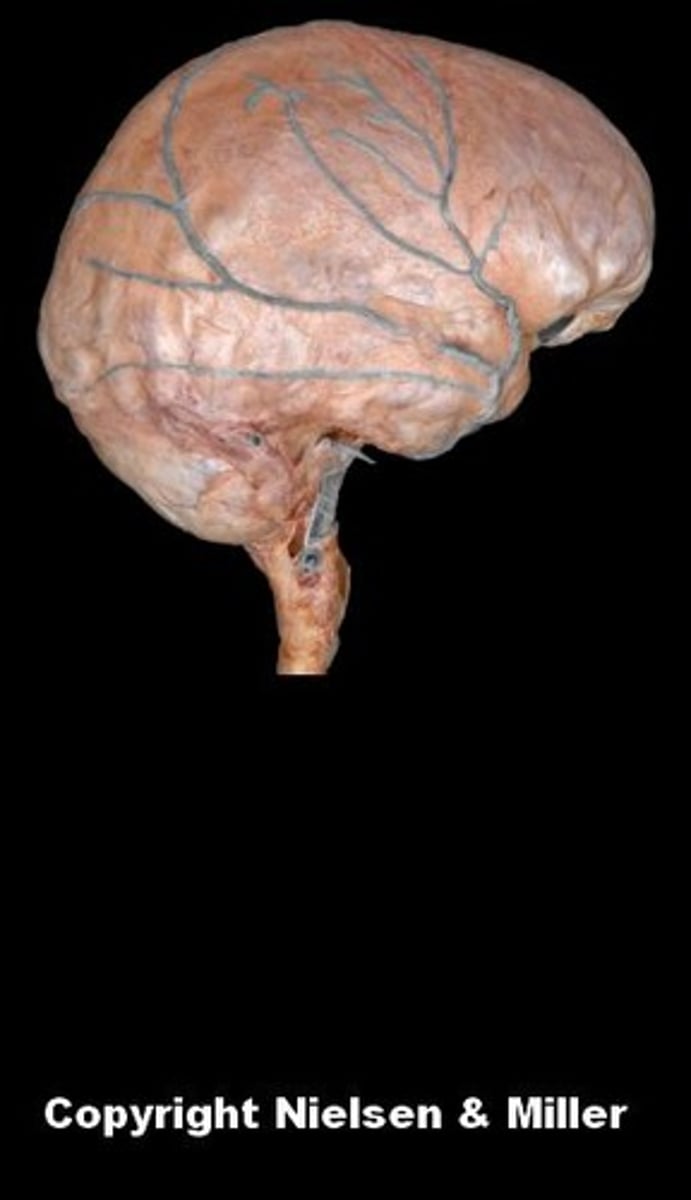

brain

cerebellum

cerebral hemispheres

cerebrum

medulla oblongata

midbrain

pons